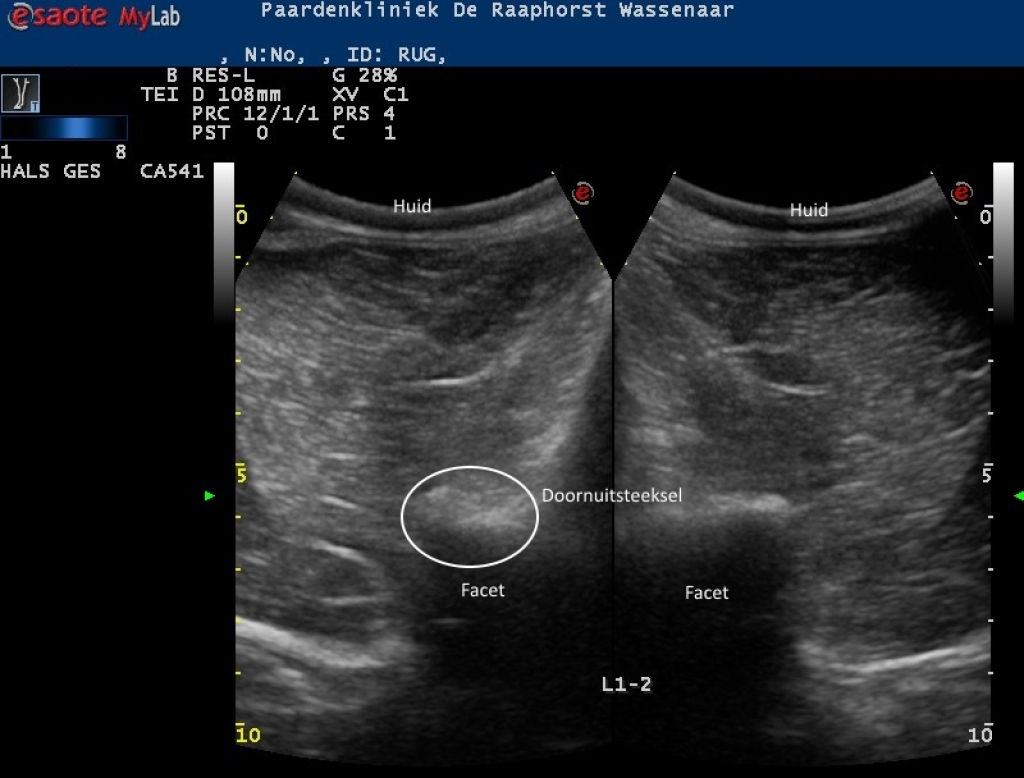

Rechts: Echografische beeld van normale facetgewricht van de lendenwervels

Echografische beeld van normale facetgewricht van de lendenwervels